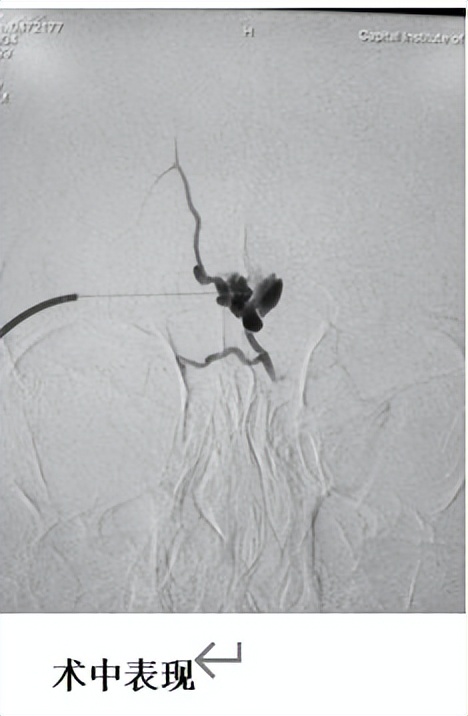

在预约好的当天,患儿在 完善术前检查后入院,第二天入介入室行介入治疗。孩子全麻下,再经皮穿刺病灶注射入硬化剂硬化治疗病灶。手术时间不长,约大概1小时,回病房后患儿卧床 12 小时,第二天就可以下床,局部病灶肿胀,压痛,无水泡坏死。顺利出院。 复查:术后 2 月后家长带着孩子来门诊复查,明显能感到患儿病灶消退,无创口,无疼痛。